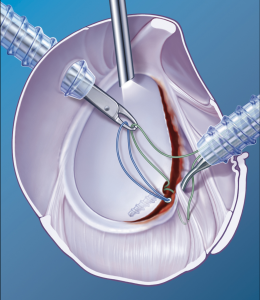

Selten kommt es zur sog. SLAP-Läsion, einer Ablösung des Bizepssehnenankers vom Pfannenrand, der arthroskopisch refixiert werden muss (Abb. 16, 17).

Auf arthroskopischem Weg kann man Bizepssehnenablösungen vom Ursprung wieder nähen (so genannter SLAP – Repair). Bei irreversiblen Schäden wird die Sehne am Ansatz durchtrennt und am Oberarmkopf arthroskopisch neu eingenäht (sog. Bizepssehnen – Tenodese) (Abb. 18). Beim älteren Patienten ohne Kraftanspruch reicht die alleinige Durchtrennung der kranken Bizepssehne (sog. Bizepssehnen – Tenotomie). Sie rutscht dann außerhalb des Gelenkes, verklemmt und vernarbt dort, es kommt zur Schmerzbefreiung.

- Arthroskopisch: Zeigt sich bei den Voruntersuchungen (Kernspin) und bei der Spiegelung ein abgelöstes Labrum (Gelenklippe) ohne wesentliche Kapselverletzung, so ist eine Refixierung des Labrums an den Pfannenrand mittels Knochenankern möglich. Zunächst wird eine diagnostische Arthroskopie (Gelenkspiegelung) zur Beurteilung des Verletzungsausmaßes des Pfannenrandes und der Kapselbandstrukturen sowie zur Beurteilung zusätzlicher Schäden durchgeführt. Anschließend erfolgt die arthroskopische Stabilisierung. Hierbei wird die abgelöste Gelenklippe (Labrum) mit dem Kapselbandapparat in ihrer ursprünglichen Position fixiert (Abb. 27 – 30).